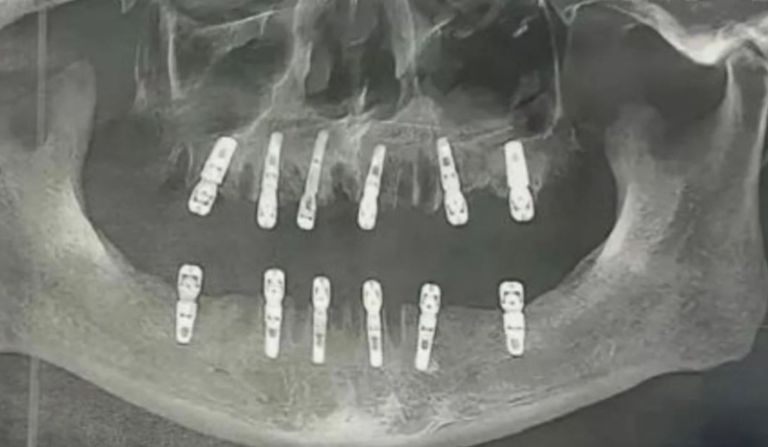

Um homem morreu 13 dias depois de extrair 23 dentes e implantar 12, na mesma cirurgia. De acordo com a mídia local, o homem foi vítima de uma parada cardíaca.

O caso foi registrado na de Yongkang Jinhua, na China, no dia 27 de agosto. A causa da morte está sendo investigada pelo Departamento Municipal de Saúde de Yongkang.

Ainda segundo informação da mídia local, o paciente assinou o termo de consentimento para a cirurgia. Após o procedimento, o homem continuou sentindo dores e morreu dias depois.

O procedimento dentário teria custado 1.500 yuans (cerca de R$ 1.185) por dente, o que equivale a aproximadamente R$ 27 mil.

Especialistas indicam que o número máximo de dentes que podem ser extraídos de uma vez chega é de 10. A filha do da vítima planeja entrar com uma ação judicial contra o hospital.